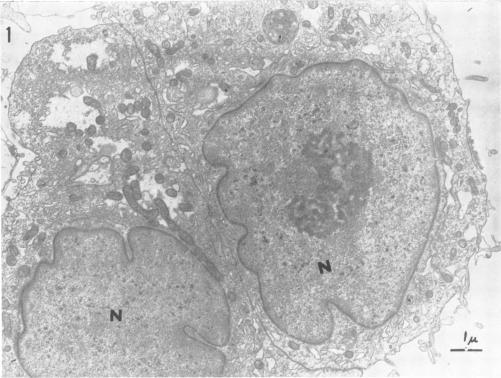

感染风疹病毒的猴肾细胞培养物的电子显微镜检查。

Electron microscopy of monkey kidney cell cultures infected with rubella virus.

Two rubella virus strains isolated in this laboratory were investigated in terms of their growth in LLC-MK(2) cell cultures and their effect on cell morphology. Rubella virus grew readily in LLC-MK(2) cells, but cytopathic effects of the virus were not observed in infected cultures. Such infected cultures can be subcultured indefinitely and continue to shed virus. Examination of rubella-infected cell cultures by electron microscopy showed the presence of annulate lamellae in the cytoplasm of 15% of the cells. No changes were evident in the nuclei. These membranous inclusions varied in complexity from parallel arrays of annulate lamellae to large lamellar structures of complex morphology. An occasional cell contained a crystal lattice structure in association with the lamellae. Larger inclusions, consisting of disorganized arrays of "unit" membranes, were also found. Uninfected cells were devoid of annulate lamellae, crystals, and complex membranous inclusions. No viruslike particles were observed in any part of the cells from infected cultures. The significance of the structures observed has not been determined.

对本实验室分离出的两株风疹病毒进行了研究,观察它们在LLC-MK(2)细胞培养物中的生长情况及其对细胞形态的影响。风疹病毒在LLC-MK(2)细胞中易于生长,但在感染的培养物中未观察到病毒的细胞病变效应。此类感染的培养物可无限传代并持续释放病毒。通过电子显微镜检查风疹感染的细胞培养物发现,15%的细胞胞质中存在环状片层。细胞核未见明显变化。这些膜性内含物的复杂程度各不相同,从平行排列的环状片层到形态复杂的大的片层结构。偶尔有细胞含有与片层相关的晶格结构。还发现了由“单位”膜无序排列组成的较大内含物。未感染的细胞没有环状片层、晶体和复杂的膜性内含物。在感染培养物的细胞任何部位均未观察到病毒样颗粒。所观察到的结构的意义尚未确定。